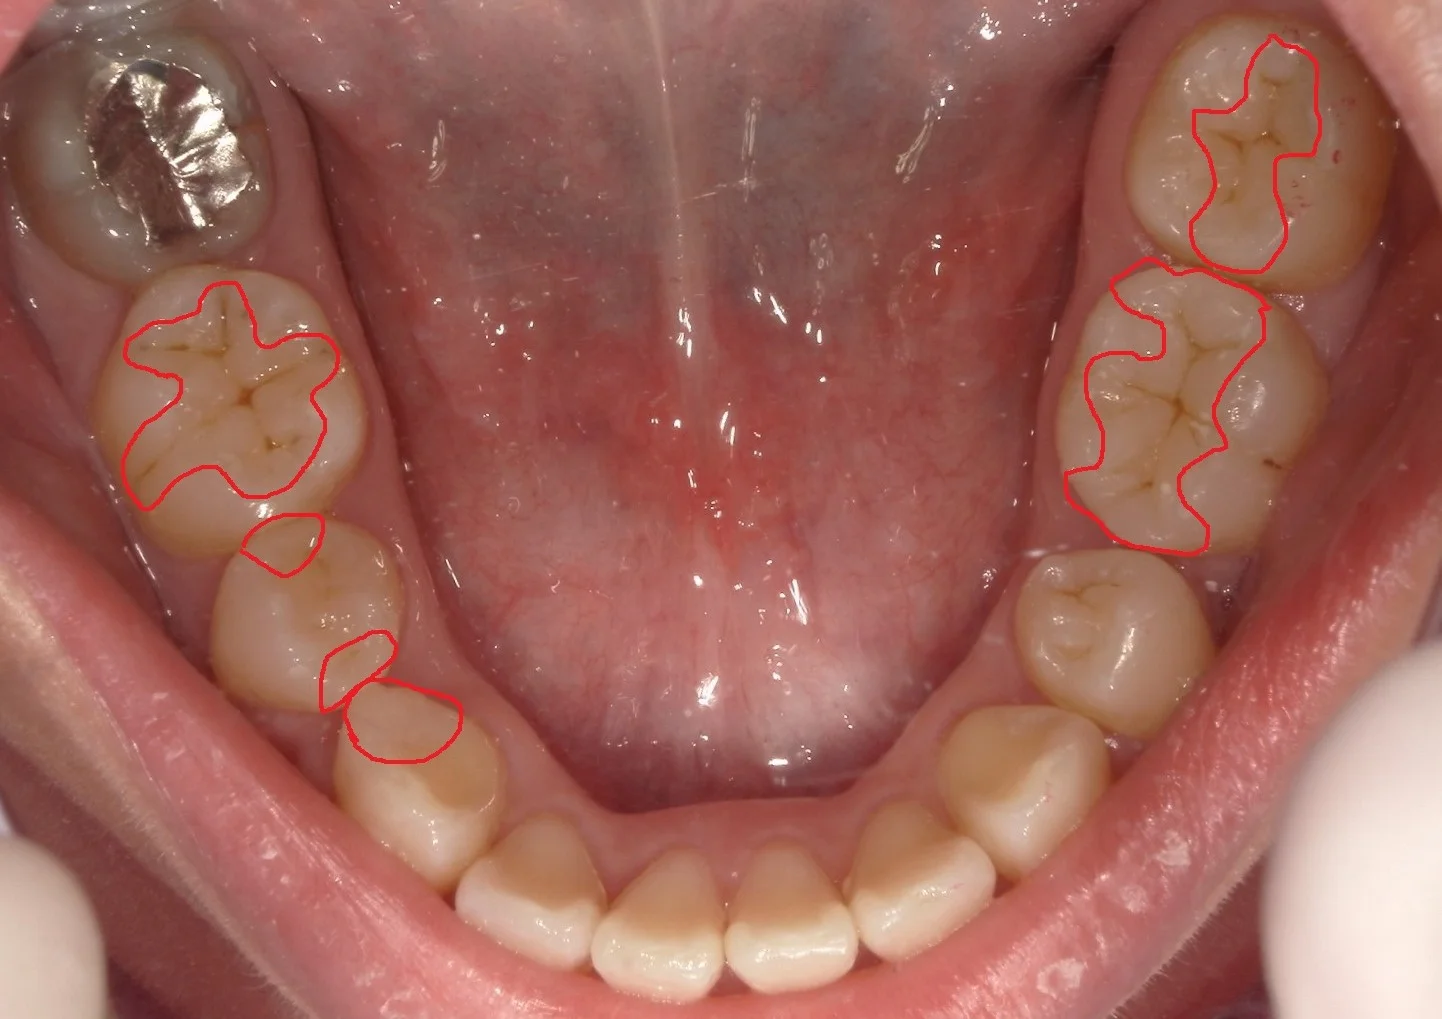

上下左右全ての部分の虫歯をセラミックを用いずにダイレクトボンディングにて治療した方のお写真を許可を頂きましたので、アップさせていただきます。

正解はこちらです!

結構たくさんの数を治してました!

患者さんは歯科医師の方なので、治療の説明などはほぼ行わず、専門用語をどんどん使って治療に入れるのでサクサクと進んでいきました(笑)

車で2時間以上掛る他県からの来院でしたので、

上下左右で計4回の来院にて治療を完了させました。

一時的に痛みが出ることが多いのですが、この方は術後に痛みなどは一切なく、終えることが出来たので、非常に感動して頂けました。